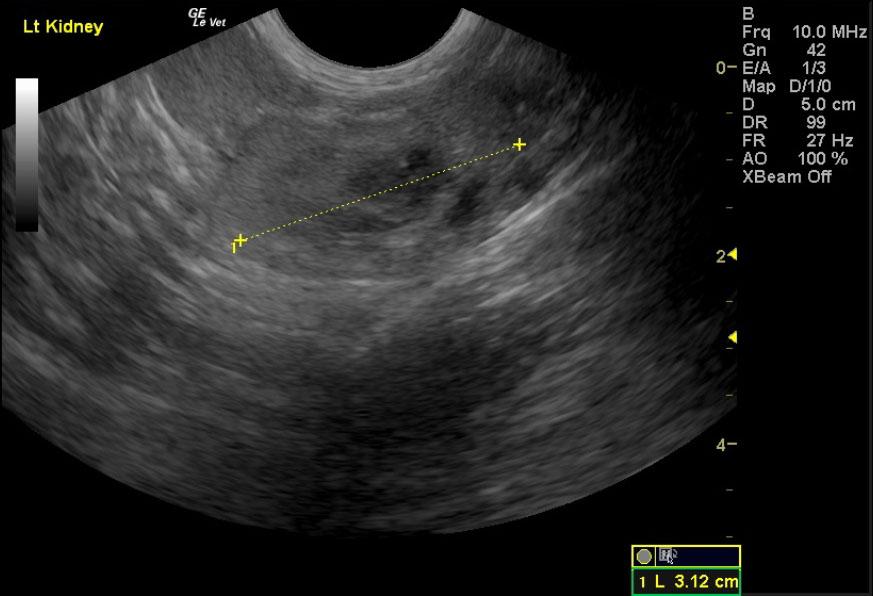

Image Interpretation

Deep right liver mass impinging upon the diaphragm and vena cava dorsally; the mass is likely not resectable. This is probably a cystadenoma, but adenocarcinoma is possible. A right perirenal cyst with a concurrent renal cortical cyst is noted in the right kidney. There is significant renal dystrophy of both kidneys, with pyelectasia or potential concurrent urinary tract infection.